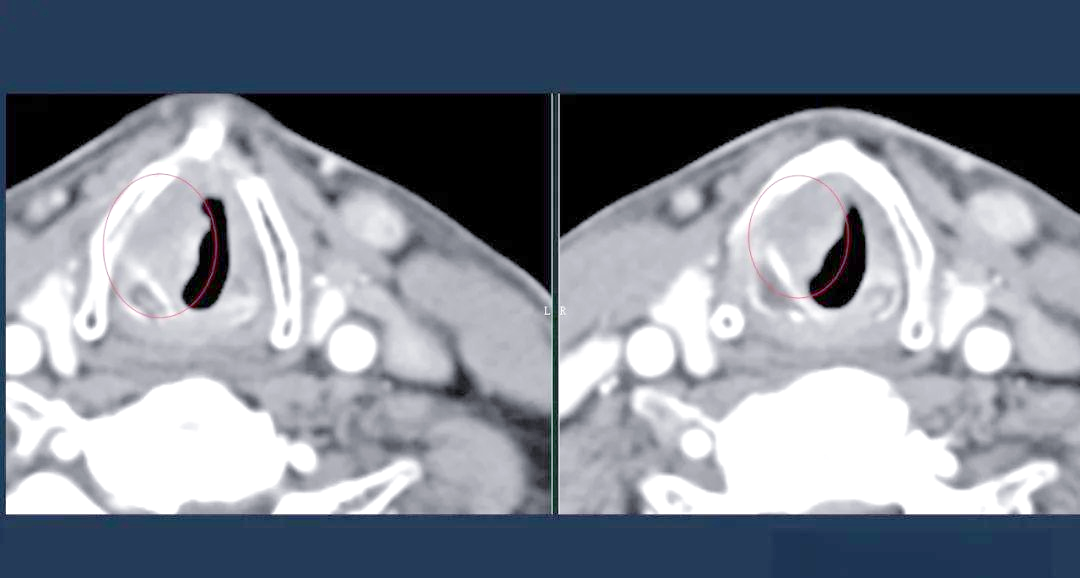

喉癌的ct,mri诊断